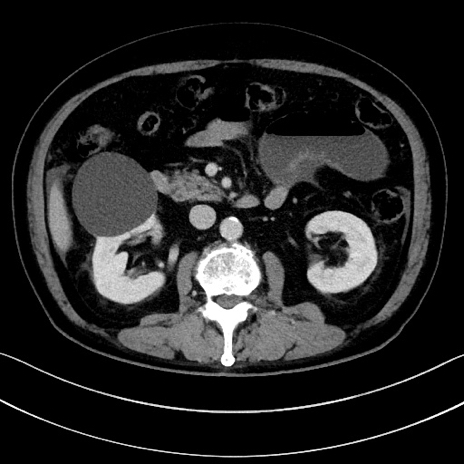

症例15(横断像)

【症例】70歳代男性

【主訴】腹痛

【現病歴】今朝から腹痛あり。全体的に痛い。特に左上の方。排ガスが今日はない。冷や汗が出る。

【既往歴】直腸癌術後

【身体所見】左側腹部〜上腹部に圧痛あり。腹膜刺激症状明らかなではない。軽度反跳痛。左下腹部に術後瘢痕あり。

【データ】WBC 7700、CRP 0.02